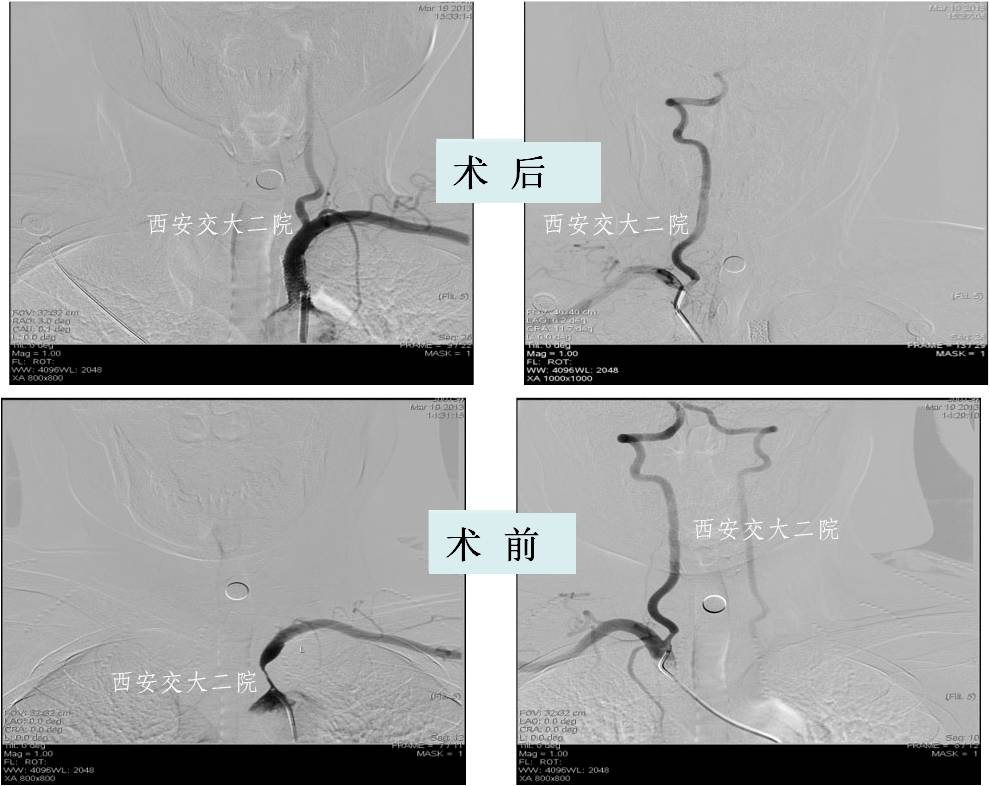

Case 2 右侧锁骨下动脉慢性闭塞再通术

》58岁,男;

》头晕、右上肢乏力4年,活动后明显;

》查体:右上肢皮温低,右侧桡动脉搏动弱,右上肢血压测不到。

Case 3 左锁骨下慢性闭塞再通(2015年)

》男,80岁,活动后头晕7年。

》5年前外院脑DSA发现左侧锁骨下动脉闭塞,右侧椎动脉开口狭窄,给予右侧椎动脉开口支架成形术,术后头晕稍有减轻,但活动后仍头晕,不能跳舞,患者坚决要求治疗。